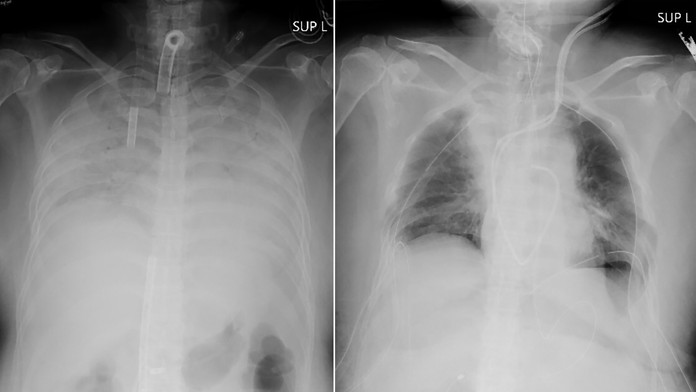

Pľúca pacientky pred transplantáciou a po nej

Pľúca pacientky pred transplantáciou a po nej Zdroj: TASR/AP